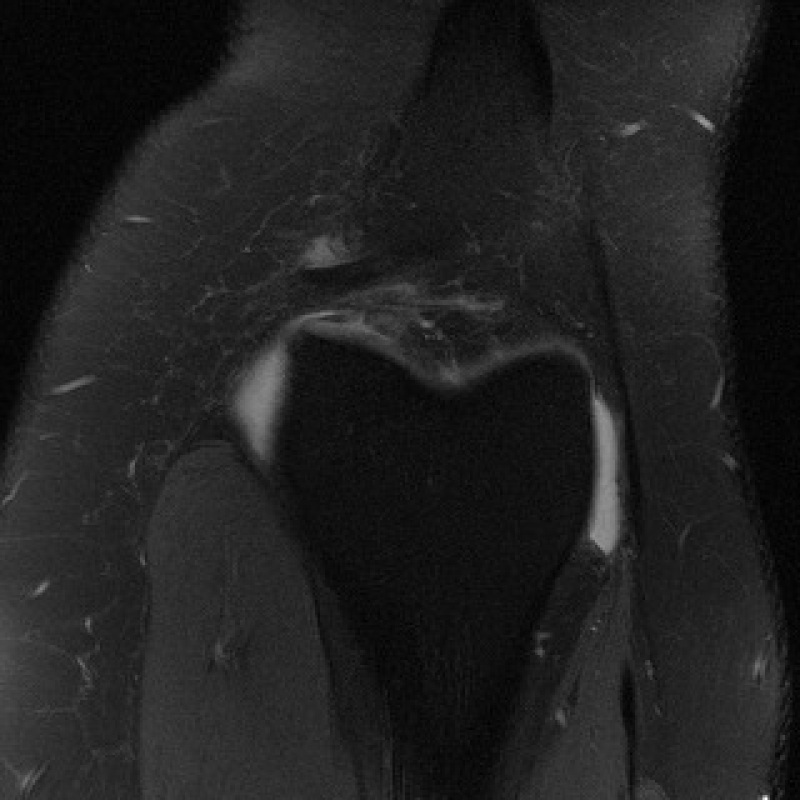

Технология строится на реконструкции изображений с помощью искусственного интеллекта. Представьте, что вы слышите начало знакомой фразы. Ваш мозг, опираясь на опыт, может точно восстановить продолжение. Аналогично ИИ, обученный на тысячах медицинских снимках МРТ, «знает», как должна выглядеть анатомия. Модель для коленного сустава обучалась на полутора тысячах других исследований. В это число вошли как итоговые снимки в формате DICOM, так и «сырые» данные (K-space). Нейросеть не «дорисовывает» наугад, а интеллектуально реконструирует качественное изображение из ограниченных данных, опираясь на медицинскую базу данных.

Помимо реконструкции снимков, технология включает модуль автоматического скрининга. Алгоритм проверяет восстановленное искусственным интеллектом изображение на наличие патологий, например, повреждения хряща, мениска и связок.

На первом этапе ученые протестировали ИИ-технологию на снимках коленного сустава из открытого набора fastMRI. Исследование показало, что восстановленные нейросетью изображения по качеству близки к стандартным МРТ-снимкам. Совместная разработка ускоряет МРТ в четыре раза. Кроме того, в систему интегрировали модуль автоматического диагностирования патологий. Он прошел верификацию на общедоступном бенчмарке MRNet.